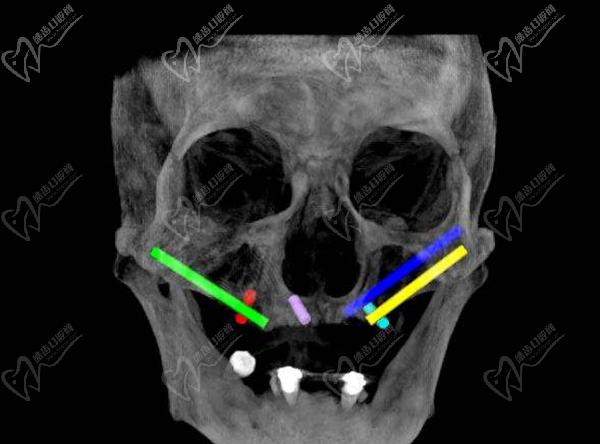

第三步:種植牙

接下來,醫(yī)生會在必要的位置上植入種植體。這些種植體充當(dāng)人工牙根,用于支撐和固定新的牙齒。采用數(shù)字化智能種植技術(shù),上下牙頜各僅需要4-6顆植體就能恢復(fù)半口牙14顆牙齒。